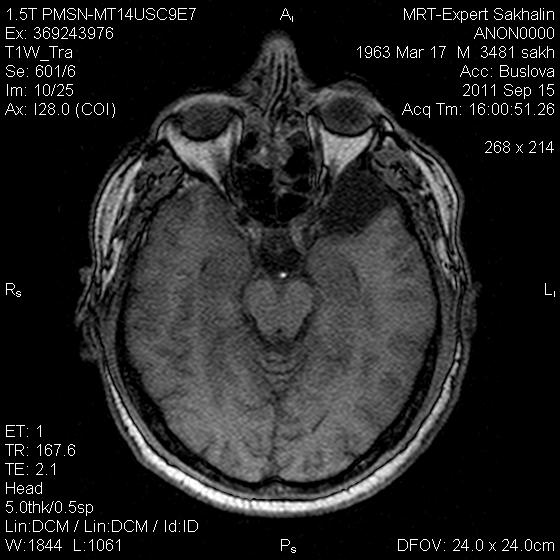

Глаз тигра?

Пациент с жалобами на головную боль.В направлении  дисциркуляторная энцефалопатия.

Первые 3 скана и есть флайер.Не только область базальных ядер ,но левая височная область.

Уж больно бросается в глаза симметричный пониженный сигнал от подкорковых образований. Я так понимаю вы пытаетесь исключить болезнь галлервордена- шпатца?

Тогда зрачка не хватает в глазу.

симметричная дегенрация подкорковых ядер -отложение депозитов железа.